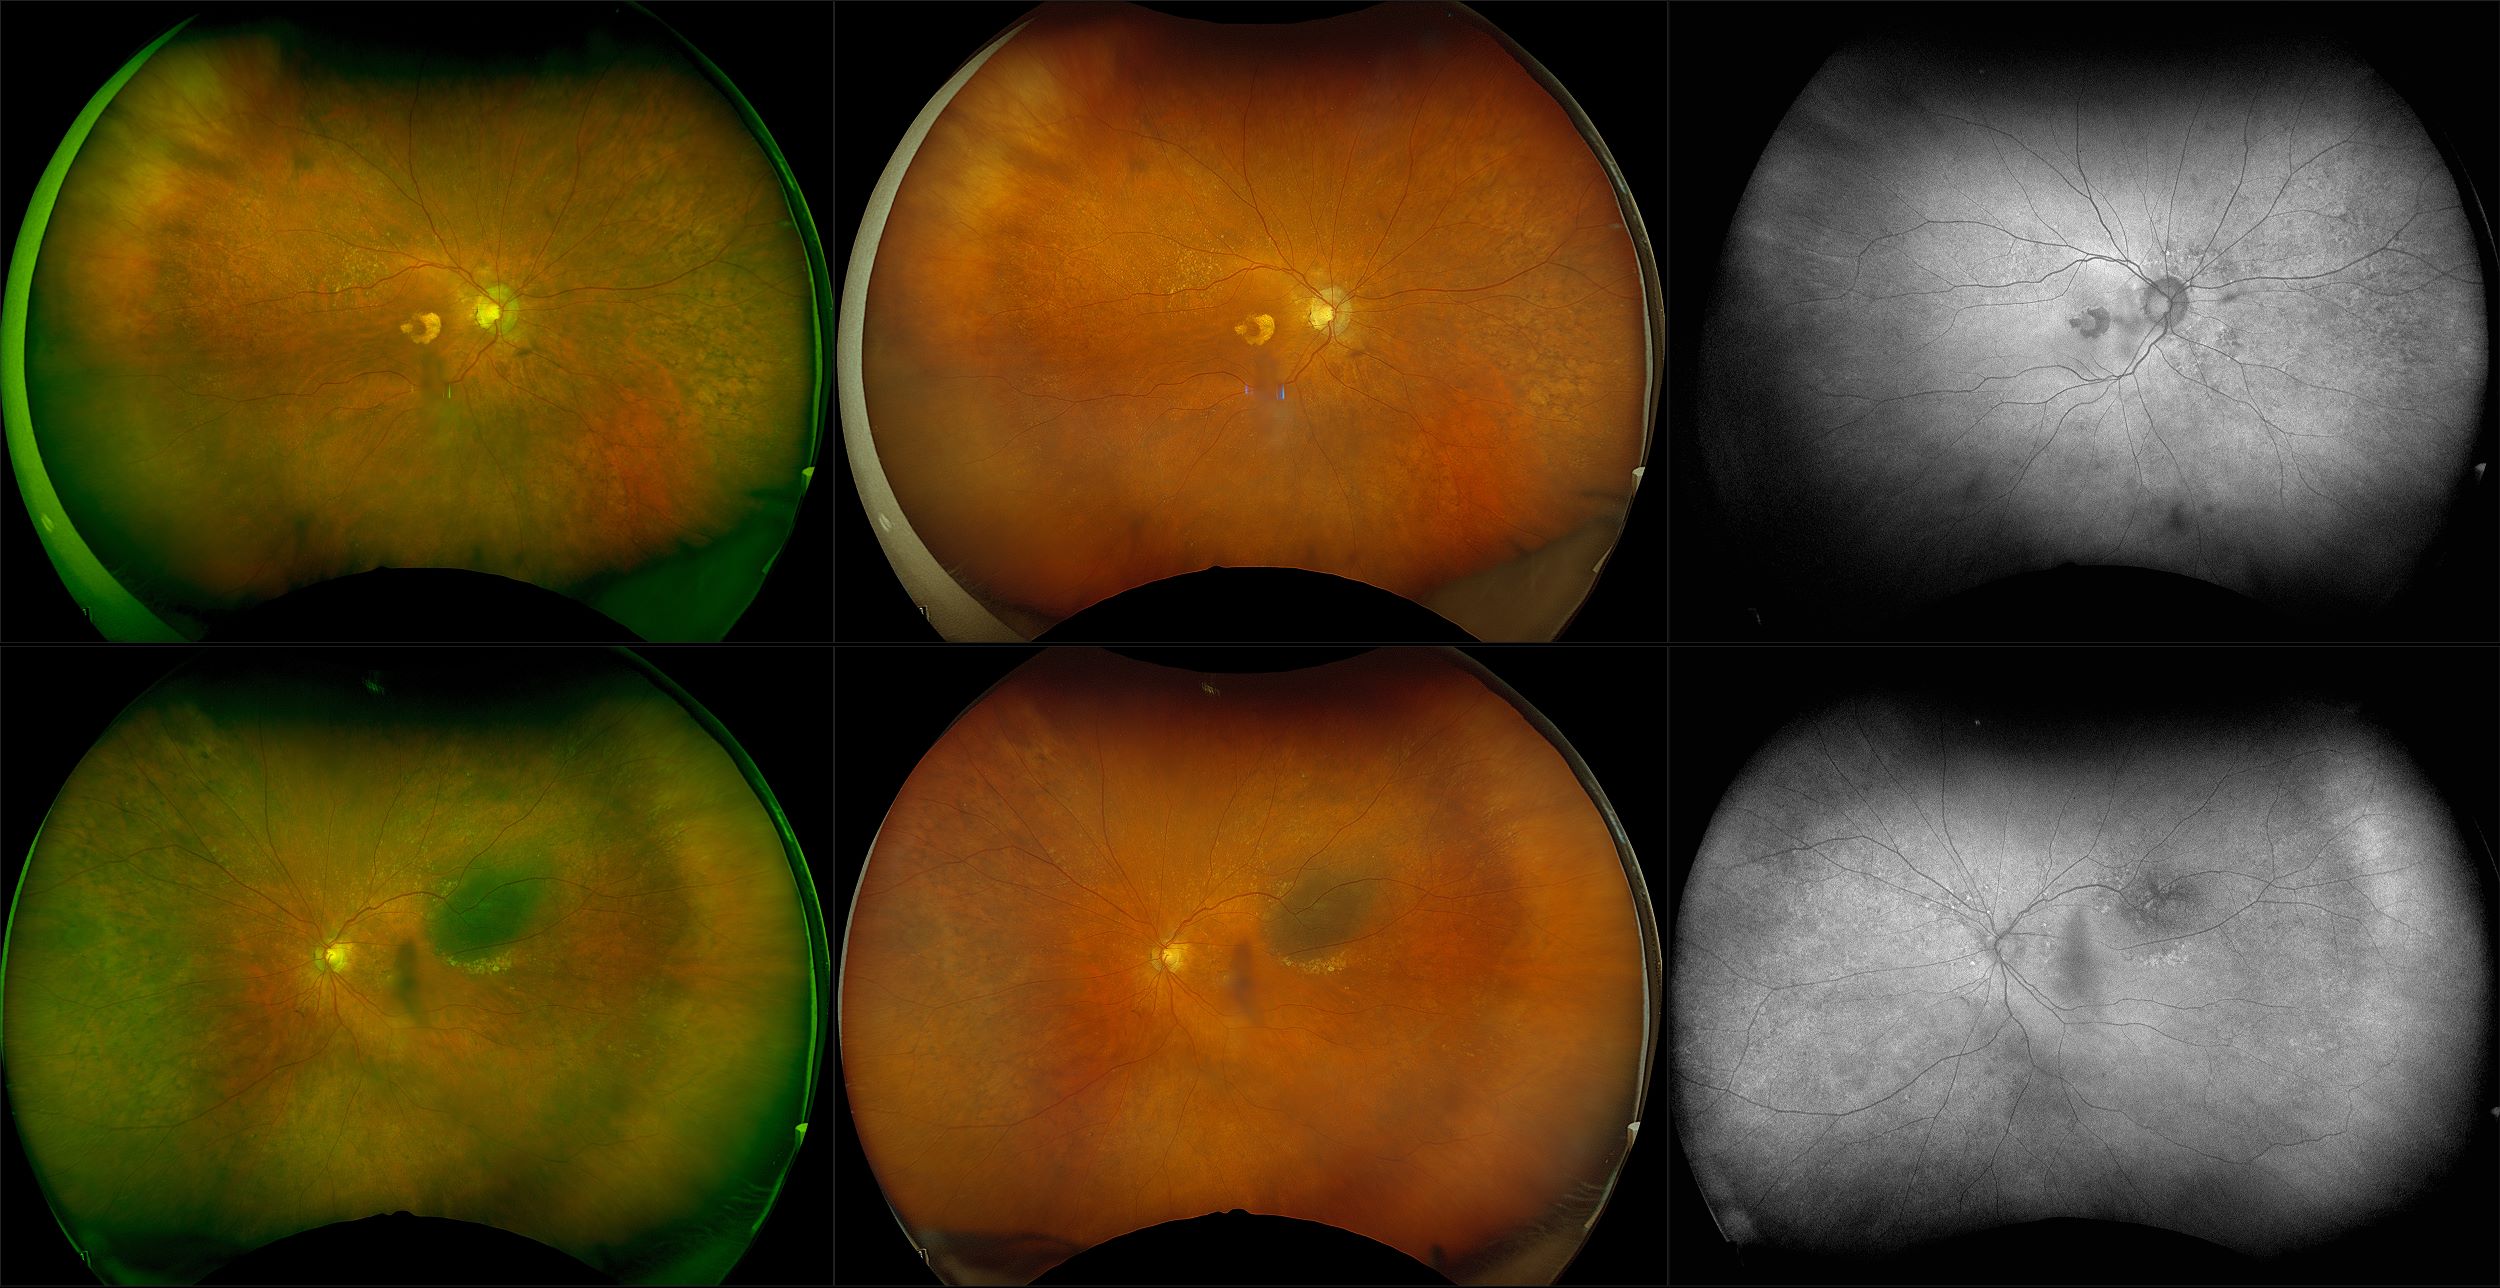

California - AMD, RG, AF

Age-related macular degeneration is found in two forms 1. Dry early form. 2. Wet (serous leakage or whole blood). Early dry form typically has drusen (usually around 63u) and RPE degeneration and only needs periodic follow-ups, intermediate dry form has large drusen (>125u) and RPE degeneration and proliferation which requires examinations every 3 to 6 months depending on the severity of the presentation.